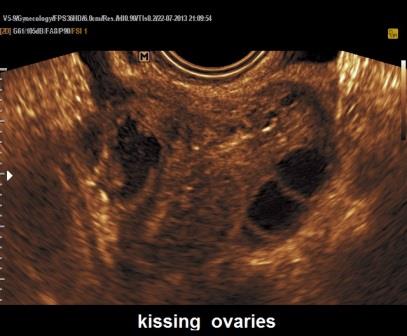

Un elemento distintivo degli endometriomi è la formazione di aderenze per cui spesso risultano fissi e dolenti alla pressione esercitata dalla sonda endovaginale. Tipicamente l'ovaio risulta ipomobile e la sonda endocavitaria non scivola lungo le pareti delle strutture contigue ("sliding sign"). Un altro segno della presenza di fenomeni aderenziali è la posizione inusuale, fissa dell'ovaio, ad esempio nel Douglas; a volte, in caso di bilateralità delle lesioni, gli endometriomi aderiscono l'un l'altro dietro l'utero "kissing ovaries".